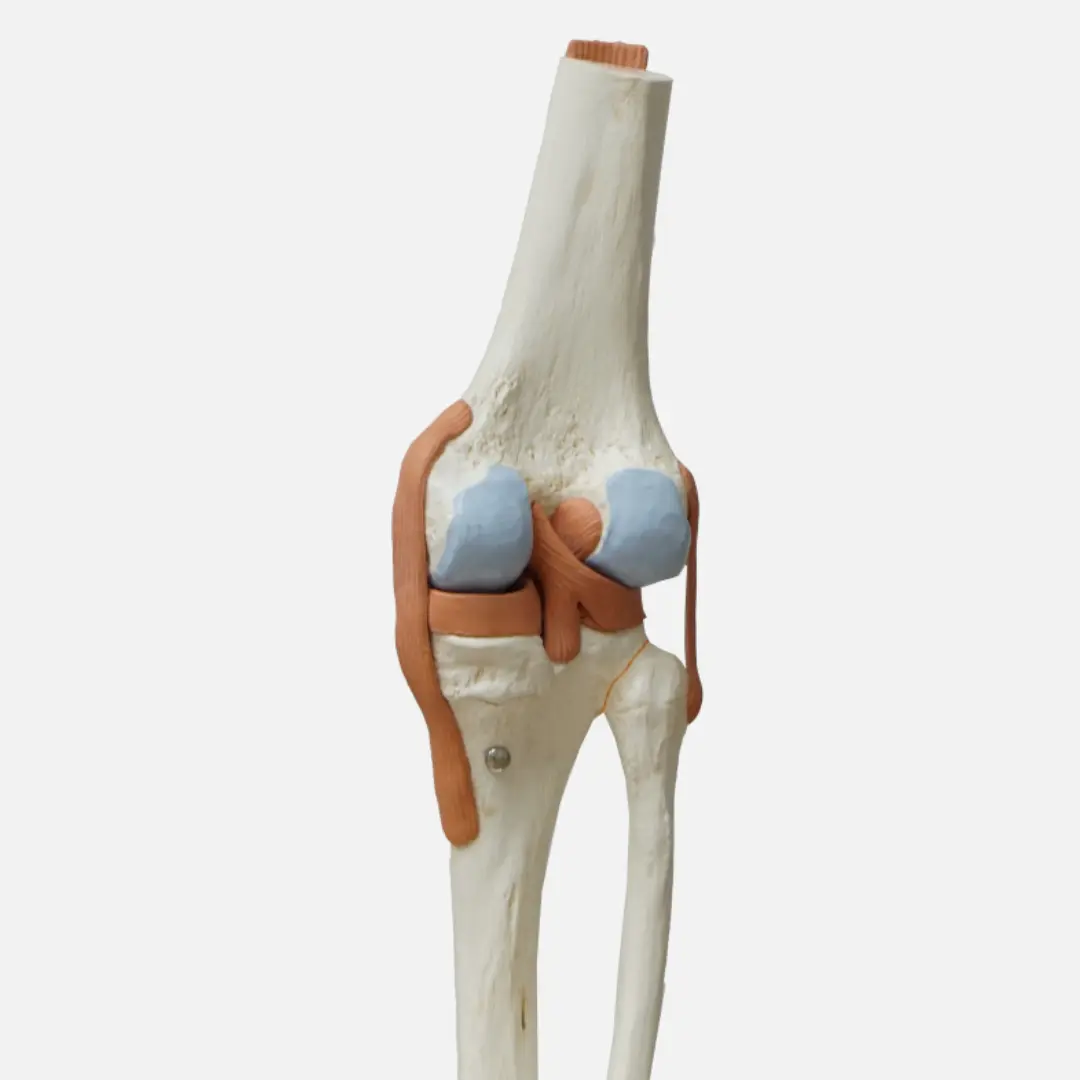

콕콕 쑤시고 욱신거리는 관절 통증 때문에 힘드시죠? 나이가 들수록, 또는 과격한 운동 후 찾아오는 관절염은 삶의 질을 뚝 떨어뜨리는 주범이 될 수 있어요. 그래서 오늘은 관절염에 좋은 음식 7가지와 그 효능, 섭취 방법, 주의사항까지 꼼꼼하게 알려드릴게요.

관절염으로 인한 염증을 줄이고 관절 건강을 증진하는 데 도움을 줄 수 있는 다양한 음식들이 우리 주변에 있어요. 꾸준한 섭취를 통해 관절 통증 완화와 기능 개선에 긍정적인 영향을 기대할 수 있답니다. 지금부터 관절염에 특히 좋은 음식 7가지를 소개해 드릴게요!